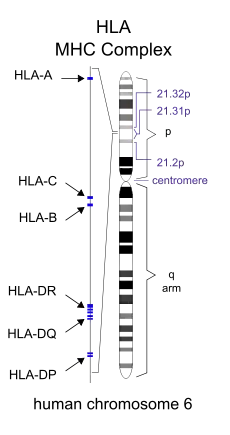

The vast majority of people with coeliac have one of two types (out of seven) of the HLA-DQ protein.[62] HLA-DQ is part of the MHC class II antigen-presenting receptor (also called the human leukocyte antigen) system and distinguishes cells between self and non-self for the purposes of the immune system. The two subunits of the HLA-DQ protein are encoded by the HLA-DQA1 and HLA-DQB1 genes, located on the short arm of chromosome 6.

There are seven HLA-DQ variants (DQ2 and DQ4–DQ9). Over 95% of people with coeliac have the isoform of DQ2 or DQ8, which is inherited in families. The reason these genes produce an increase in the risk of coeliac disease is that the receptors formed by these genes bind to gliadin peptides more tightly than other forms of the antigen-presenting receptor. Therefore, these forms of the receptor are more likely to activate T lymphocytes and initiate the autoimmune process.[28]

Most people with coeliac bear a two-gene HLA-DQ2 haplotype referred to as DQ2.5 haplotype. This haplotype is composed of two adjacent gene alleles, DQA1*0501 and DQB1*0201, which encode the two subunits, DQ α5 and DQ β2. In most individuals, this DQ2.5 isoform is encoded by one of two chromosomes 6 inherited from parents (DQ2.5cis). Most coeliacs inherit only one copy of this DQ2.5 haplotype, while some inherit it from both parents; the latter are especially at risk for coeliac disease as well as being more susceptible to severe complications.[64]

Some individuals inherit DQ2.5 from one parent and an additional portion of the haplotype (either DQB1*02 or DQA1*05) from the other parent, increasing risk. Less commonly, some individuals inherit the DQA1*05 allele from one parent and the DQB1*02 from the other parent (DQ2.5trans) (called a trans-haplotype association), and these individuals are at similar risk for coeliac disease as those with a single DQ2.5-bearing chromosome 6, but in this instance, the disease tends not to be familial. Among the 6% of European coeliacs that do not have DQ2.5 (cis or trans) or DQ8 (encoded by the haplotype DQA1*03:DQB1*0302), 4% have the DQ2.2 isoform, and the remaining 2% lack DQ2 or DQ8.[65]

The frequency of these genes varies geographically. DQ2.5 has high frequency in peoples of North and Western Europe (Basque Country and Ireland[66] with highest frequencies) and portions of Africa and is associated with disease in India,[67] but it is not found along portions of the West Pacific rim. DQ8 has a wider global distribution than DQ2.5 and is particularly common in South and Central America; up to 90% of individuals in certain Amerindian populations carry DQ8 and thus may display the coeliac phenotype.[68]

Other genetic factors have been repeatedly reported in coeliac disease; however, involvement in disease has variable geographic recognition. Only the HLA-DQ loci show a consistent involvement over the global population.[69] Many of the loci detected have been found in association with other autoimmune diseases. One locus, the LPP or lipoma-preferred partner gene, is involved in the adhesion of extracellular matrix to the cell surface, and a minor variant (SNP=rs1464510) increases the risk of disease by approximately 30%. This gene strongly associates with coeliac disease (p < 10−39) in samples taken from a broad area of Europe and the US.[69]